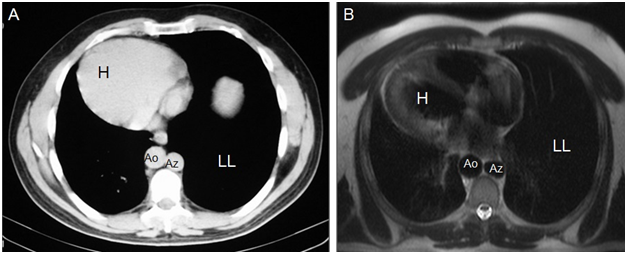

Dextrocardia with cardiac apex to the right (Figures 4) (Figure 8).

Figure 8Axial CT (A) and MR (B) images show dextrocardia and cardiac apex on the right (H), aorta on the right (Ao), azygos vein on the left (Az), and a larger left lung (LL).

1. Posible bilobed right lung (smaller size and right bronchus more horizontal) and trilobed left lung (larger size and left bronchus vertical) (Figures 4, 7 & 8).

2. Aorta on the right with aortic arch over the right bronchus (Figures 3, 4, 6, 7 & 8).

6. Venous drainage from the abdomen is carried by the azygos system (azygos vein to the left of the thoracic aorta). Azygos arch is over the left bronchus (Figures 3, 4 & 8).